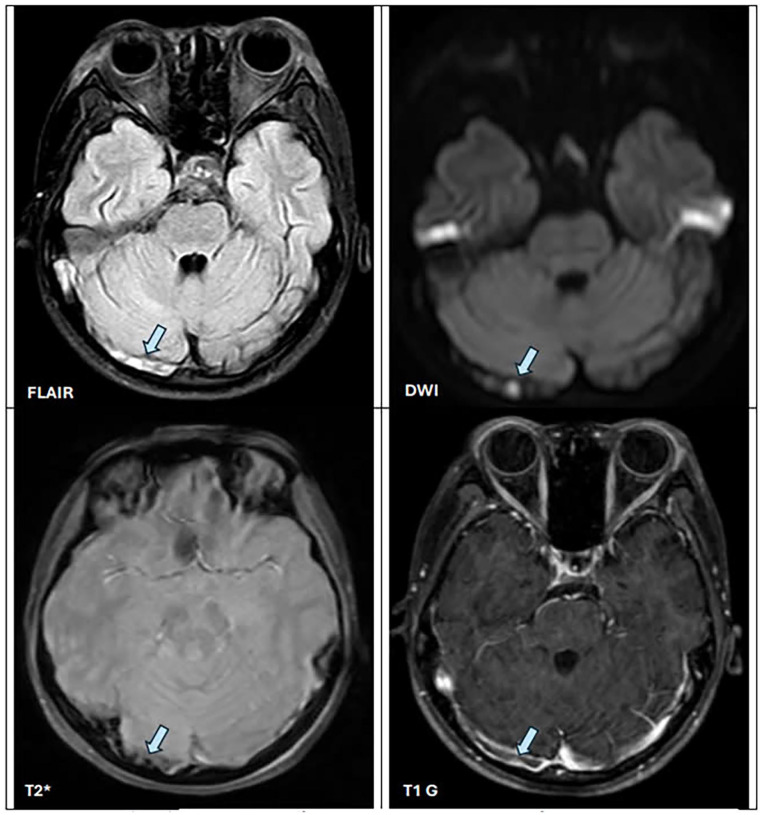

蛋白质丢失性肠病(PLE)是一种罕见但公认的系统性红斑狼疮(SLE)的表现。作为SLE的初始表现,PLE非常罕见,特别是在儿科患者中。我们报告一名15岁的越南女孩,没有明显的既往病史或家族史,她以le作为SLE的初始表现。临床特征包括双眼睑和下肢水肿、腹水和低白蛋白血症,无肾性蛋白尿、肝功能障碍或营养不良。粪便α1-抗胰蛋白酶浓度明显升高,为bb0 231 mg/dL(正常0.5 g/24 h),符合2019年EULAR/ACR SLE分类标准。患者还出现脑静脉窦血栓形成。用皮质类固醇、羟氯喹和华法林治疗可显著改善临床症状。随访7个月,患者临床稳定,血清白蛋白水平正常化,血栓消退。本病例强调了在资源有限的情况下将PLE诊断为SLE的初始症状所面临的挑战。提高对这种罕见表现的认识可以促进早期诊断和最佳管理,改善患者预后。

Protein-losing enteropathy (PLE) is a rare but recognized manifestation of systemic lupus erythematosus (SLE). As an initial presentation of SLE, PLE is exceptionally uncommon, particularly in pediatric patients. We report the case of a 15-year-old Vietnamese girl with no significant past medical or family history, who presented with PLE as the initial manifestation of SLE. Clinical features included bilateral eyelid and lower extremity edema, ascites, and hypoalbuminemia, in the absence of nephrotic-range proteinuria, hepatic dysfunction, or malnutrition. Stool α1-antitrypsin concentration was markedly elevated at >231 mg/dL (normal <26.8 mg/dL), supporting the diagnosis of PLE in conjunction with clinical features and therapeutic response. Immunological evaluation revealed positive antinuclear antibody (ANA), anti-double-stranded DNA (anti-dsDNA) antibody, and lupus anticoagulant, hypocomplementemia, along with proteinuria equivalent to >0.5 g/24 h, fulfilling the 2019 EULAR/ACR classification criteria for SLE. The patient also developed cerebral venous sinus thrombosis. Treatment with corticosteroids, hydroxychloroquine, and warfarin resulted in significant clinical improvement. At 7 months of follow-up, she remained clinically stable, with normalized serum albumin levels and resolution of thrombosis. This case highlights the challenges of diagnosing PLE as an initial symptom of SLE in resource-limited settings. Heightened awareness of this rare presentation can facilitate early diagnosis and optimal management, improving patient outcomes.